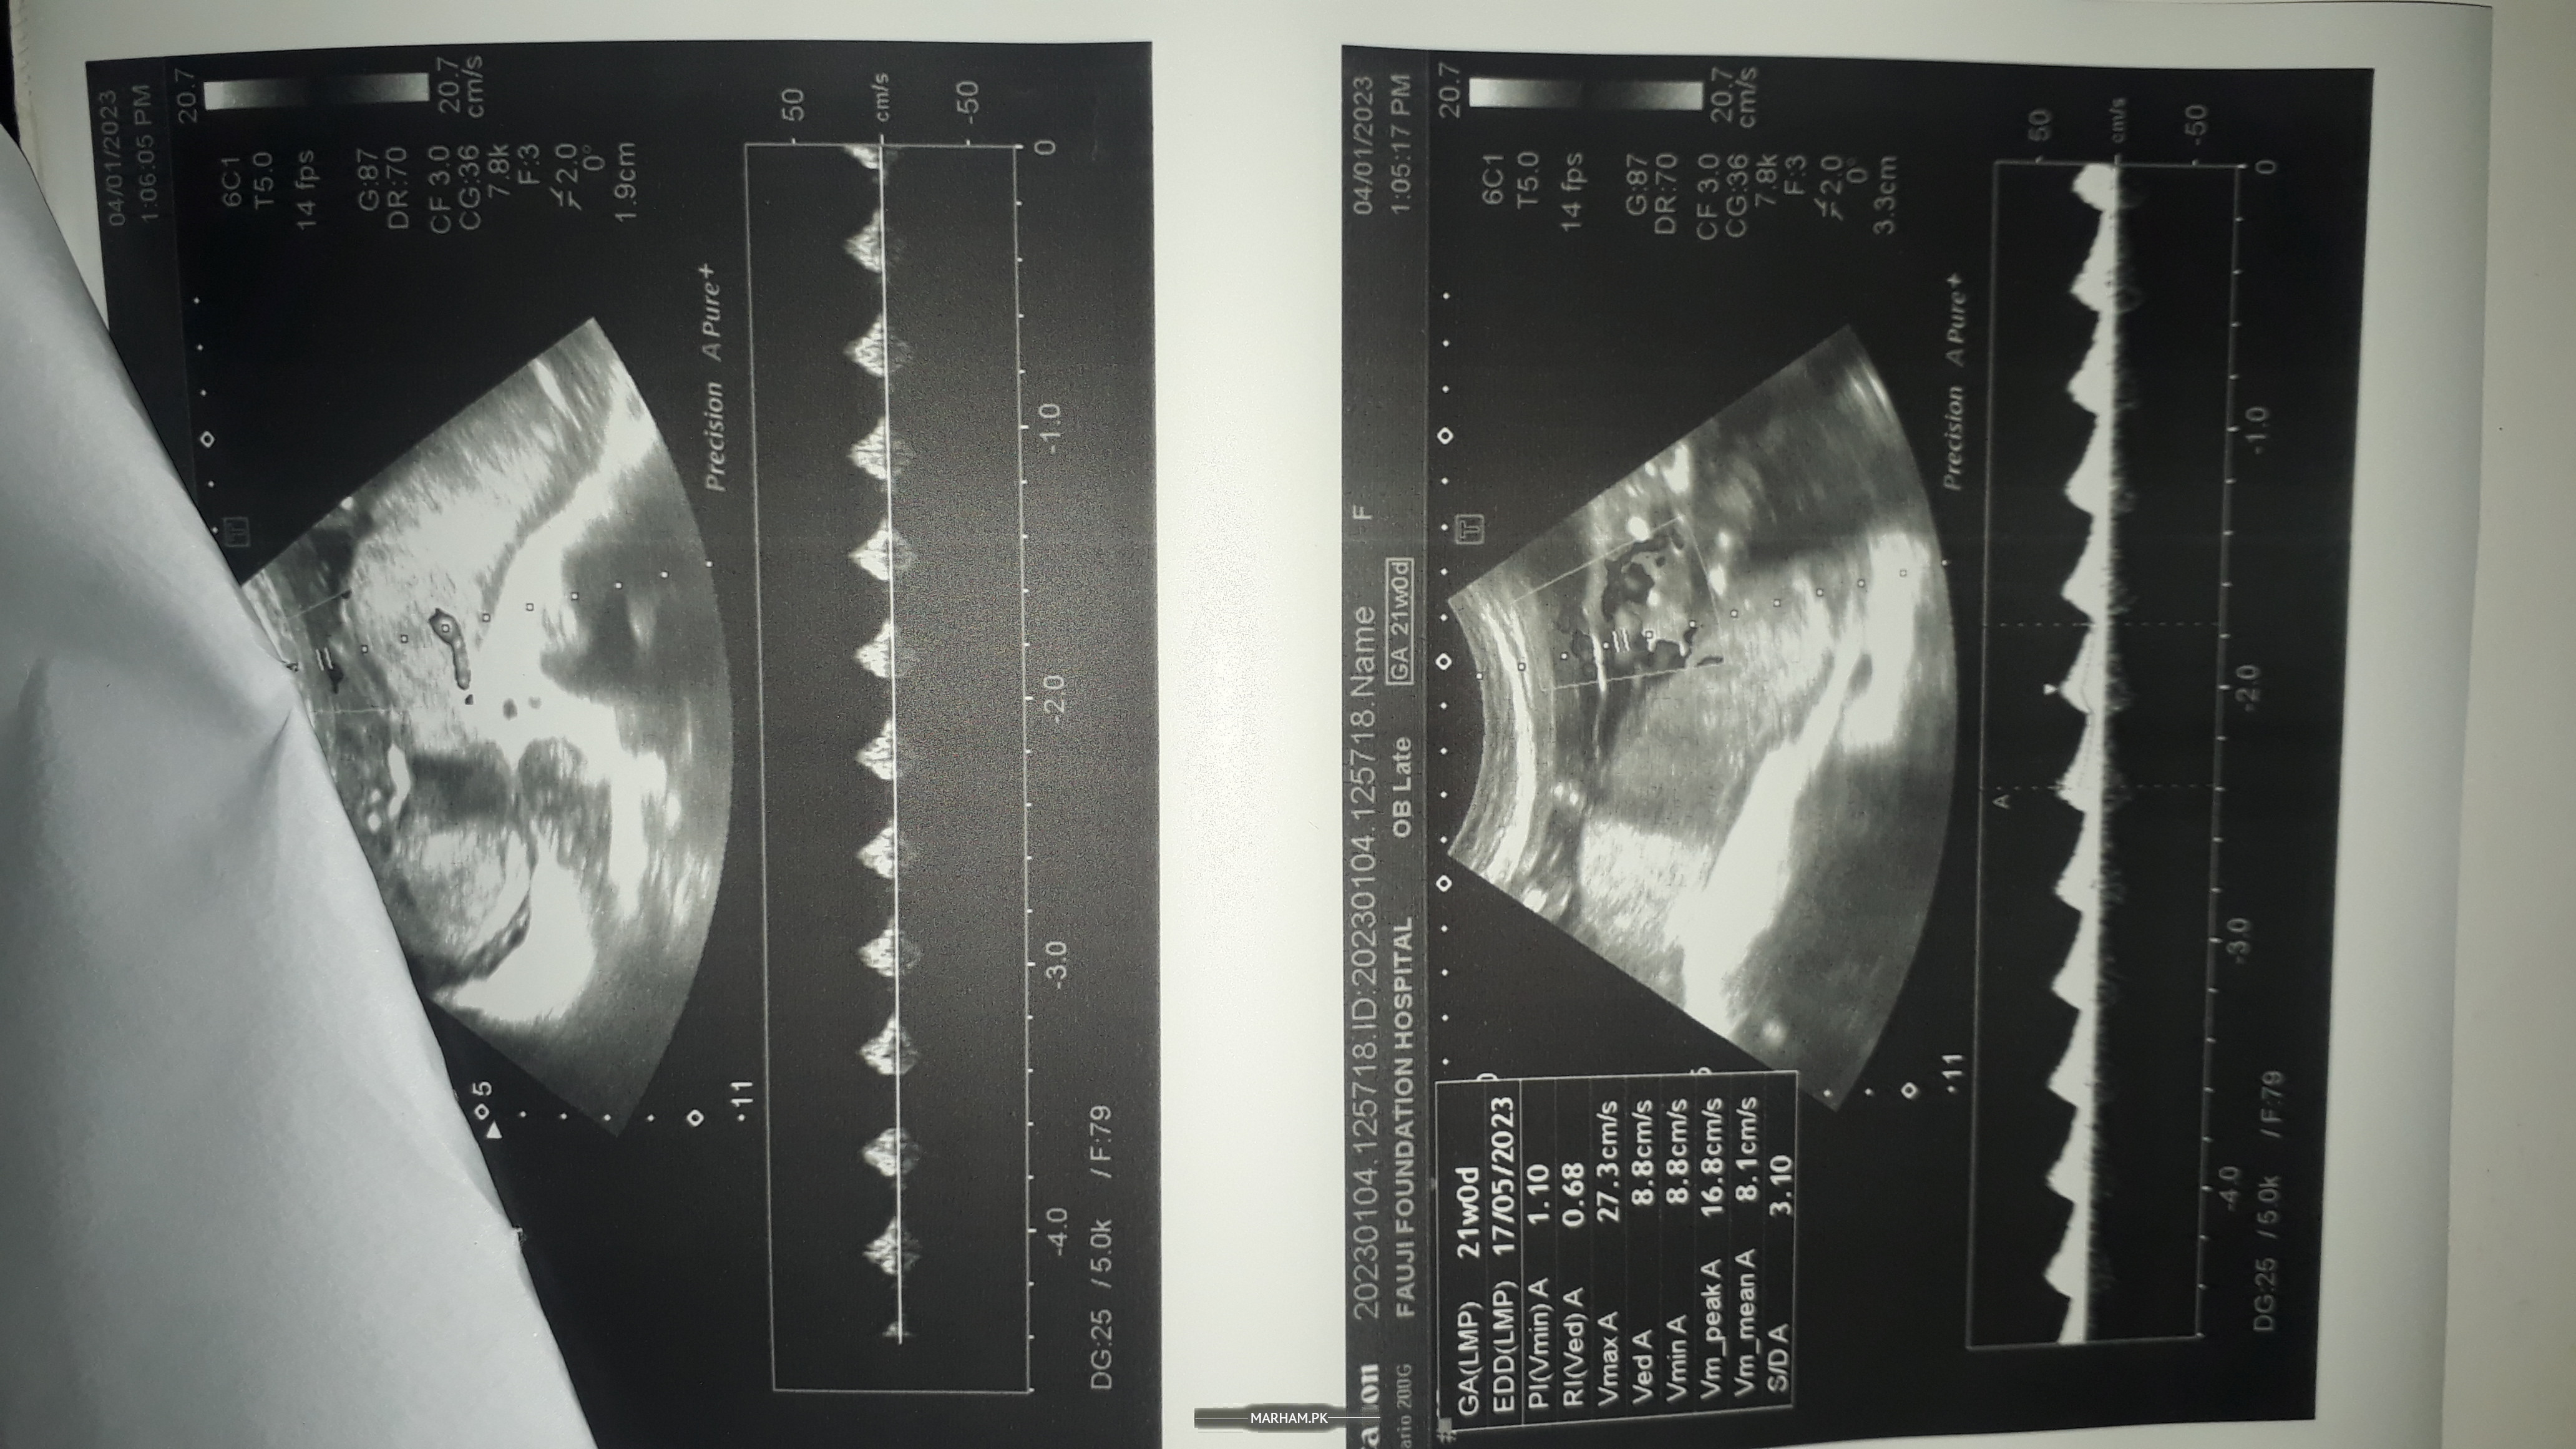

uterine artery doppler ultraound

chk my ultrasound

kindly meri report chk kr k bta dein

my report

b ultrasound

report

Share your ultrasound report

kindly baby gender bi bta dein ultrasound dekh k